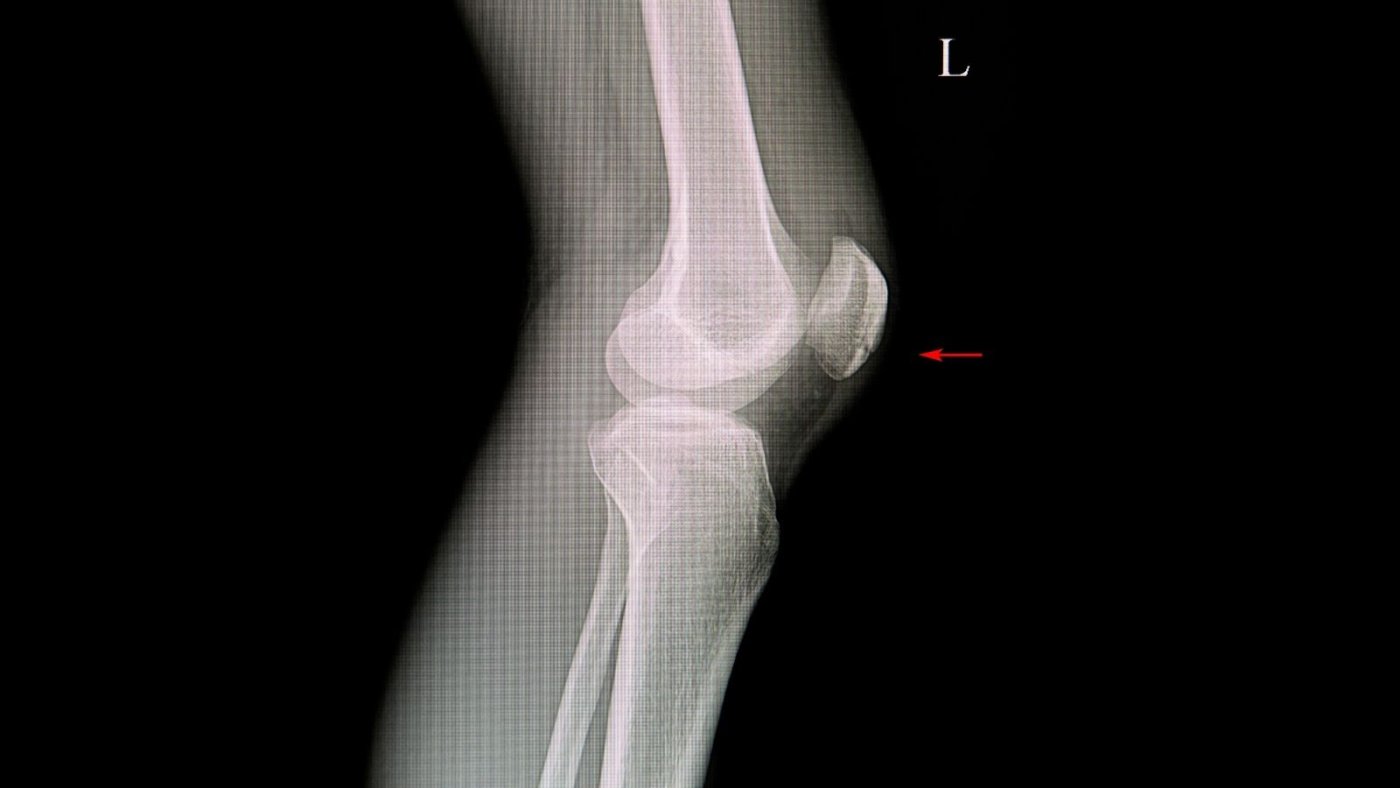

Patella (diz kapağı), diz ekleminin ön kısmında yer alan ve dizin düzgün çalışmasında önemli rol oynayan bir kemiktir. Quadriceps kası ile birlikte çalışarak dizin açılmasını sağlar ve yürüyüş, merdiven çıkma gibi günlük hareketlerde kritik bir görev üstlenir. Travmalar, düşmeler veya direkt darbe sonucu patella kırıkları meydana gelebilir ve bu durum diz fonksiyonlarını ciddi şekilde etkileyebilir.

Patella, diz ekleminin önünde yer alan küçük ama fonksiyonel açıdan oldukça önemli bir kemiktir. Quadriceps kasının tendonları içinde yer alır ve dizin açılma hareketine yardımcı olur.

Patella Kırıkları Neden Oluşur?

Patella kırıkları genellikle yüksek enerjili travmalar sonucu oluşur. En sık görülen nedenler şunlardır:

• Diz üzerine direkt darbe

• Düşmeler

• Trafik kazaları

• Spor yaralanmaları

Bazı durumlarda ani kas kasılması da patella kırığına neden olabilir. Özellikle osteoporoz gibi kemik yoğunluğunu azaltan durumlarda kırık riski artar.